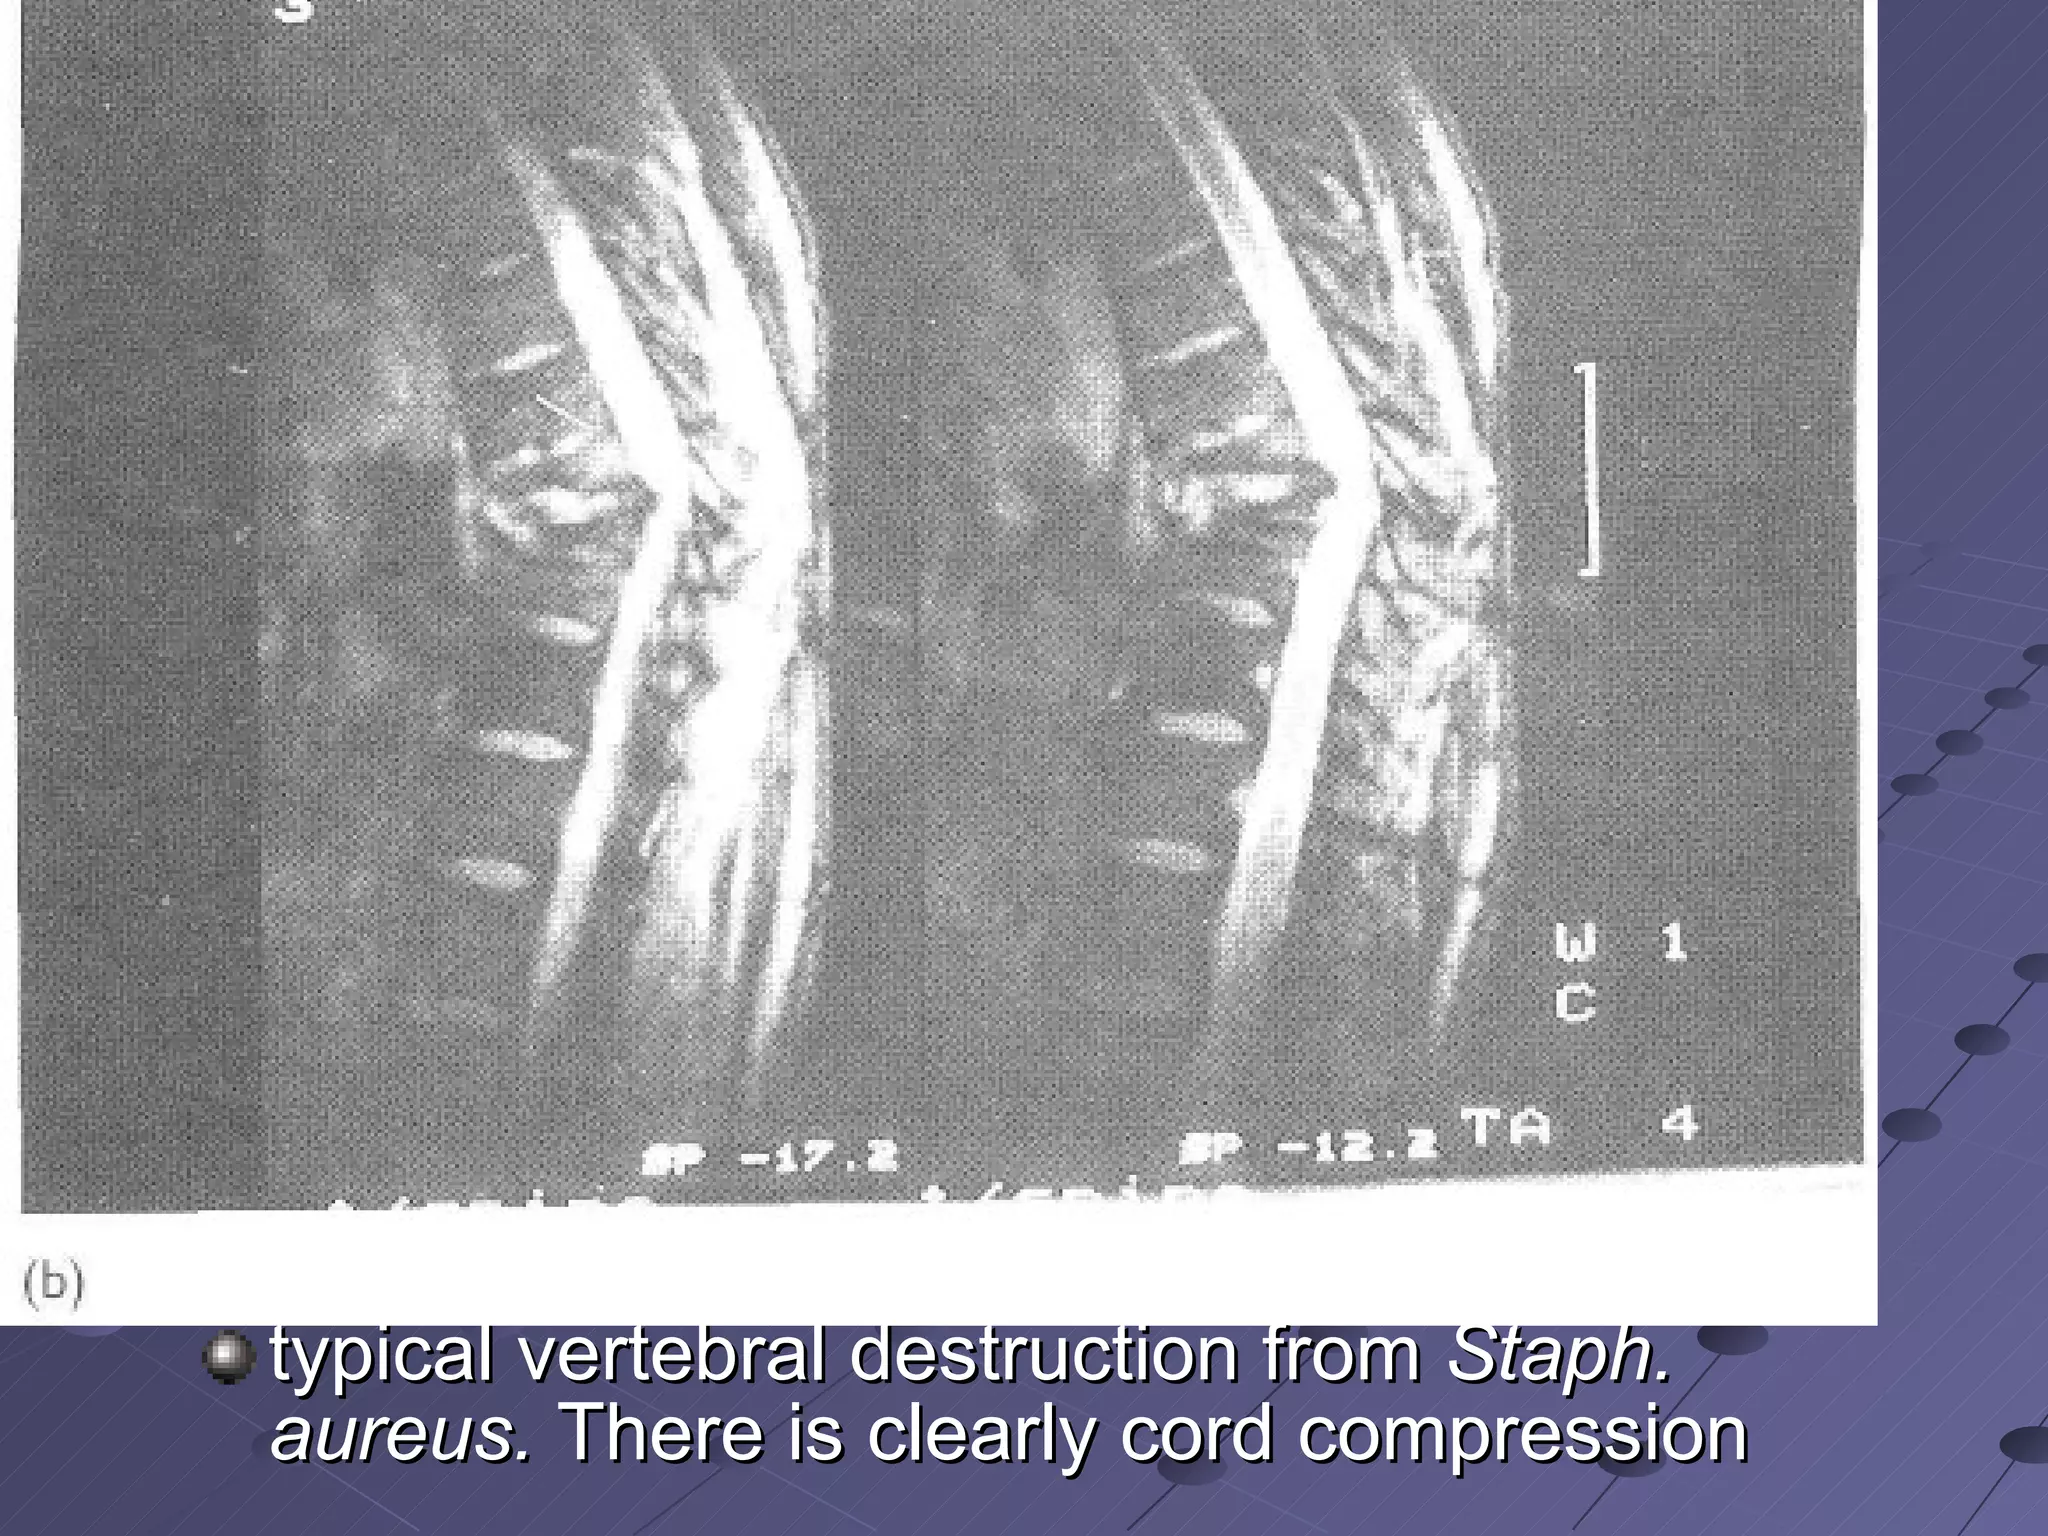

MRI scanning most important investigation  sensitivity of 96% specificity …up to 95%  MRI shows the soft tissue well, including the neural components defines abscess cavities precisely

thoracic diskitis with an associated epidural abscess and spinal cord compression

typical vertebral destruction from  Staph. aureus.  There is clearly cord compression

MRI scanning mostimportant investigation sensitivity of 96% specificity …up to 95% MRI shows the soft tissue well, including the neural components defines abscess cavities precisely

thoracic diskitis withan associated epidural abscess and spinal cord compression

typical vertebral destructionfrom Staph. aureus. There is clearly cord compression